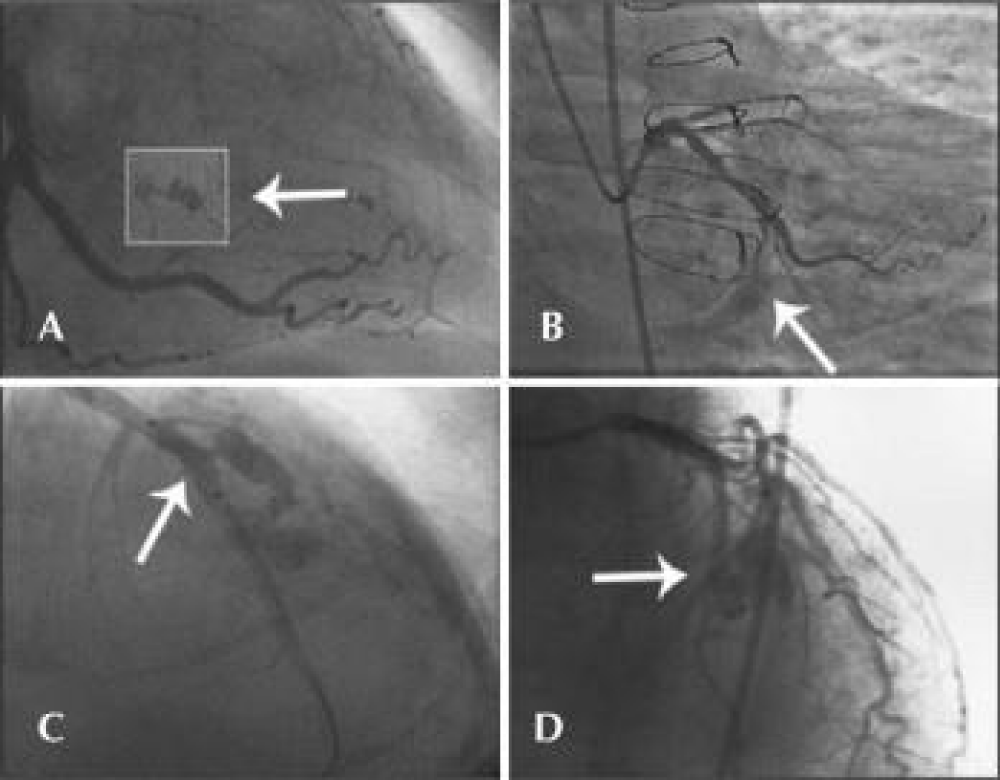

If sudden and very severe chest pain occurs during percutaneous coronary angioplasty, always keep in mind the possibility of coronary artery perforation. In this situation, the balloon should be left in the guiding catheter until verification by angiography. Once this complication is confirmed, the balloon should be inflated immediately at the perforation site. Coronary angiography is still the gold standard for the diagnosis of CAP. The modified Ellis classification is used to stratify coronary perforations (Figure 1).

Type I CAP is characterized by an extraluminal crater with no linear contrast extravasation that suggests dissection. Type II CAP is characterized by myocardial or pericardial blushing. Type III CAP is characterized by frank contrast medium extravasation into the pericardium. Type IV cap is characterized by perforation with contrast extravasation directly into the left ventricle, to the coronary sinus or other vascular [3].